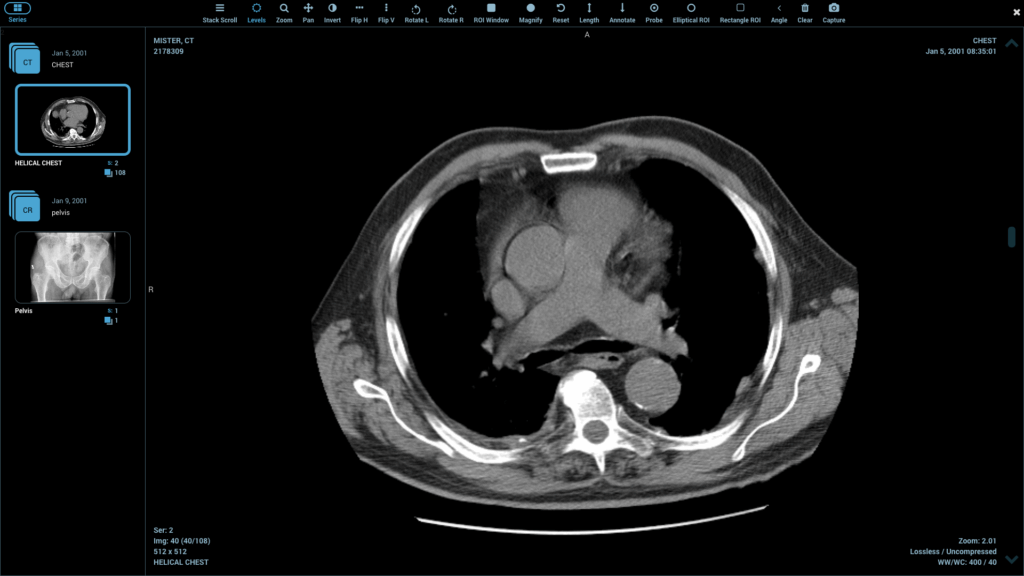

You can’t write an accurate report if you can’t see the details. A robust DICOM viewer is as essential as a sharp microscope is to a pathologist.

Modern viewers go beyond simple display. They offer features that directly contribute to diagnostic confidence. Look for tools like adjustable windowing and leveling to bring out subtle contrast differences, zoom functions for a closer look at fine details, and side-by-side comparison for tracking changes over time. These technical capabilities are your first line of defense against perceptual errors.

A powerful viewer transforms a static image into a dynamic dataset you can explore. Don’t settle for a viewer that feels clunky or limited. The right tool should feel like an extension of your own vision, helping you isolate and interrogate findings with precision.